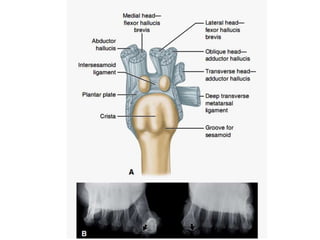

SUBLUXACION DE LA CABEZA

DE M1 SOBRE SESAMOIDEO

SUBLUXACION DE LA CABEZA DE M1 SOBRE SESAMOIDEO

SUBLUXACION DE MF1

ARTROSIS DE MF1

BURSITIS INFLAMATORIA DOLOR INFECCION POSIBLE SUBLUXACIONDE LA CABEZA DE M1 SOBRE SESAMOIDEO SUBLUXACION DE MF1 ARTROSIS DE MF1 DESPLAZAMIENTO LATERAL DE LOS DEDOS CONTIGUOS